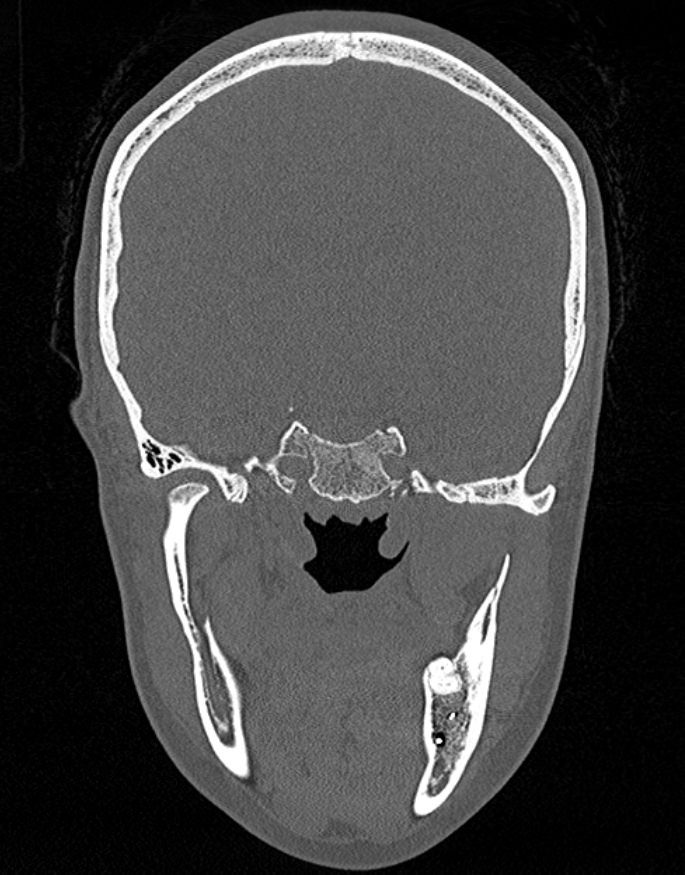

Мультиспиральная компьютерная томография относится к высокоинформативным лучевым методам исследования, то есть основана на применении рентгеновского излучения и различной способности тканей поглощать рентгеновские лучи. Костные структуры обладают наибольшей плотностью по сравнению с другими тканями, поэтому в большей степени поглощают рентгеновские лучи и лучше всего визуализируются при данном исследовании. Благодаря этому КТ позволяет детально изучить кости лицевого черепа, а также углубления, которые являются вместилищем для важных органов (глазницы, полость носа, ротовая полость).

КТ мягких тканей лица является наиболее информативным методом диагностики травматических повреждений лица, посттравматических деформаций, аномалий развития, инородных предметов в носовой полости и околоносовых пазухах. Кроме того, мультиспиральная КТ применяется для выявления скрытых воспалительных процессов, нарушений кровообращения в области лица, а также используется при планировании оперативного вмешательства (в том числе, пластических операций) и в дальнейшем применяется в послеоперационном периоде для оценки успешности проведенной операции.

Детальные изображения костей лицевого черепа и мягких тканей лица получаются за счет вращения трубки томографа с излучателями рентгеновских лучей вокруг объекта исследования. В аппаратах увеличено количество сверхчувствительных детекторов, позволяющих производить множество послойных снимков с толщиной среза от 0,5 мм, которые затем преобразуются в трехмерные пространственные модели лицевого черепа с окружающими тканями. Такие инновационные возможности аппаратов обеспечивают проведение точной и достоверной диагностики.